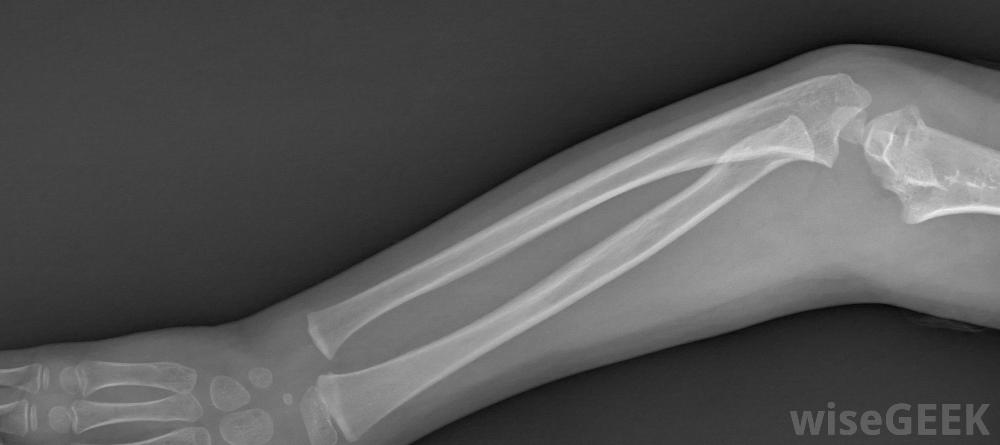

臂叢神經是從脊髓開始的一組神經,控制著身體中的肩、手和手臂肌肉。如果這些神經群受傷,一個人的手臂可能會感到麻木、劇烈疼痛、虛弱或失去活動能力。在較小的情況下,當臂神經受傷時,身體能夠自行愈合臂叢神經損傷。通常有兩種治療方法:物理治療和外科手術。物理療法是治療臂叢損傷的兩種主要方法之一為了確定對病人的適當治療,醫生通常會首先進行一系列的檢查。如果傷情發生后立即對患者進行評估,以獲得最佳的臂叢治療效果,通常情況下,檢查首先要對受傷的手臂進行身體檢查和x光檢查。為了幫助診斷,醫生可以要求進行肌電圖(EGM)測試,這包括將一個小電極針插入皮膚來測試肌肉及其神經。神經科醫生通常會檢查結果并確定神經損傷的嚴重程度。臂叢神經治療通常從對受傷手臂進行x光檢查開始,大多數人選擇物理療法作為臂叢神經治療的形式物理治療的時間長短通常取決于損傷的嚴重程度和患者的進展情況。臂叢神經的鍛煉可以包括各種手臂伸展、手和手腕的鍛煉,以及不同范圍的運動練習。這些運動可以防止手臂僵硬,有助于增強手臂,一旦病人接受了專業理療師的訓練,他們通常會被鼓勵在家里做同樣的運動。在更嚴重的情況下,手術是臂叢神經治療的主要方式患者在接受物理治療后無法恢復,通常在受傷后的三到六個月內進行手術。有幾種手術可以修復或替換受損的神經,可以通過神經移植和神經轉移來完成。手術后,許多人在物理治療后的兩到六個月內就可以恢復手臂的完全活動。臂叢神經損傷的人不應該放棄充分利用受傷的手臂。為了完全康復,通常是這樣最好聽從醫生的指示。通常建議患者認真對待物理治療練習或手術,不要過度勞累他們的損傷。